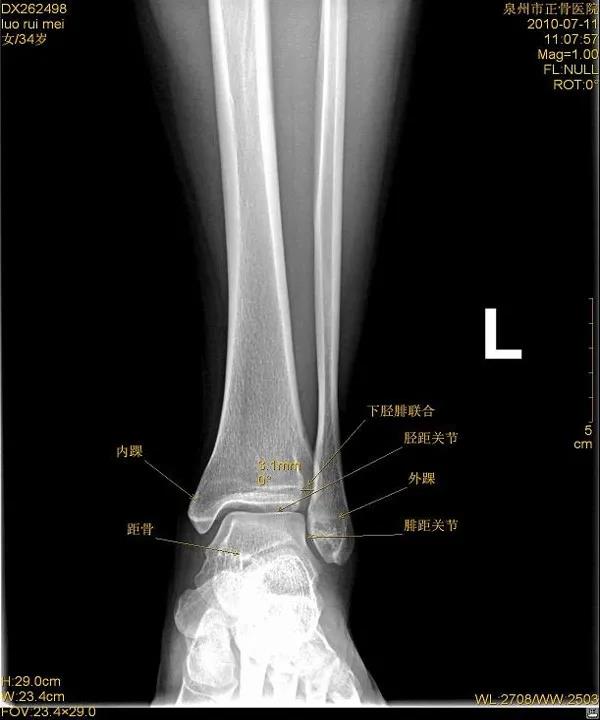

X线

踝关节正位